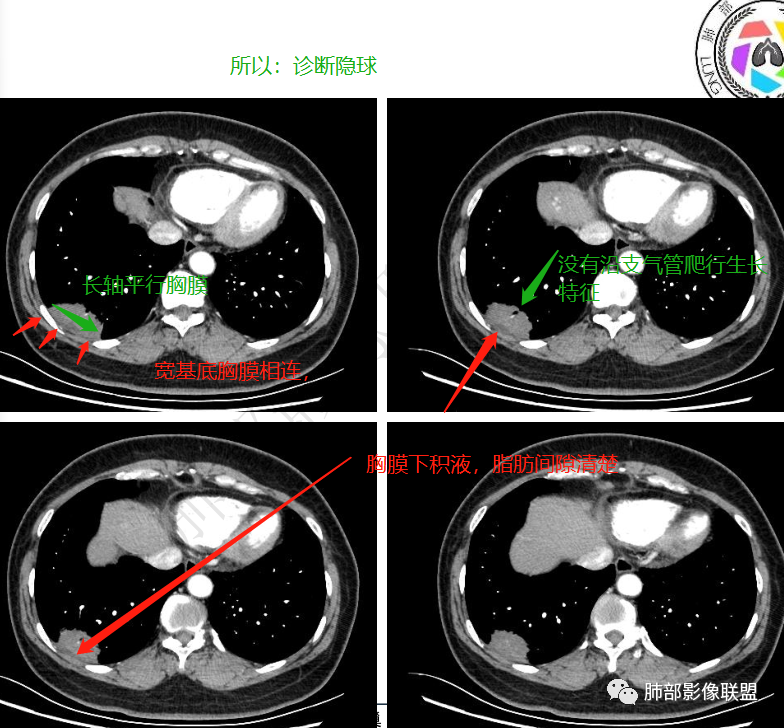

无症状体检发现右肺下叶不规则后基底段胸膜下实变影,整体边界清楚,部分有磨玻璃影,边界平直收缩,长轴平行胸膜,内部见支气管进入后截断,内部密度不均匀,增强扫描轻度不均匀强化,考虑炎性病变,隐球菌可能,鉴别腺癌

左肺下叶胸膜下团块影,长轴平行胸膜,边缘清晰,可见磨玻璃影,支气管进去后截断,胸膜糊墙,增强后轻度强化。考虑炎性肉芽肿病变,隐球可能。

冯连彩:

体检发现,年龄不祥,右肺下叶靠近胸膜下实性肿块,长轴与胸膜平行,边缘光滑,无明显分叶及毛刺,边缘平直为主,支气管进入后截断,轻中度强化,胸膜下脂肪间隙清晰,考虑良性病变,炎性肉芽肿可能,鉴别肺癌。